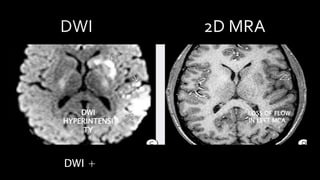

FLAIR +

PATCHY

HYPERINTENSITY LINEAR HYPOINTENSITY

IN LEFT MCA

DWI +

DWI

HYPERINTENSI

TY

LOSS OF FLOW

• #52 DWI of the same patient shows multiple patchy foci of diffusion restriction consistent with ACUTE CEREBRAL INFARCTION. AXIAL 2D MRA shows no flow in the left MCA